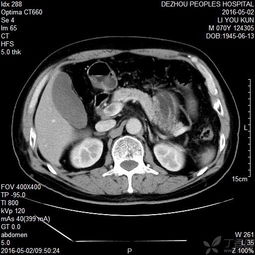

肺癌轉(zhuǎn)移現(xiàn)為腦水腫有何中藥治療?回答者:蘇振超你好,建議住院觀察,遵醫(yī)囑治療目前